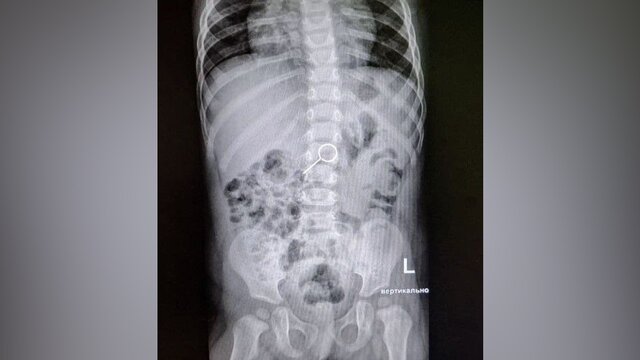

11-месячная девочка поступила в Детскую больницу № 9 имени Г. Н. Сперанского после того, как проглотила ключ-скрепку от сим-карты. Врачи помогли избавить ее от инородного предмета в желудке, сообщила пресс-служба учреждения.

Врачи сделали рентген и выявили, что инородный предмет проскользнул в желудок. В связи с этим медики решили сделать маленькой пациентке очистительную клизму. В результате ключ-скрепка смогла покинуть организм ребенка без других вмешательств, и девочку выписали из больницы.